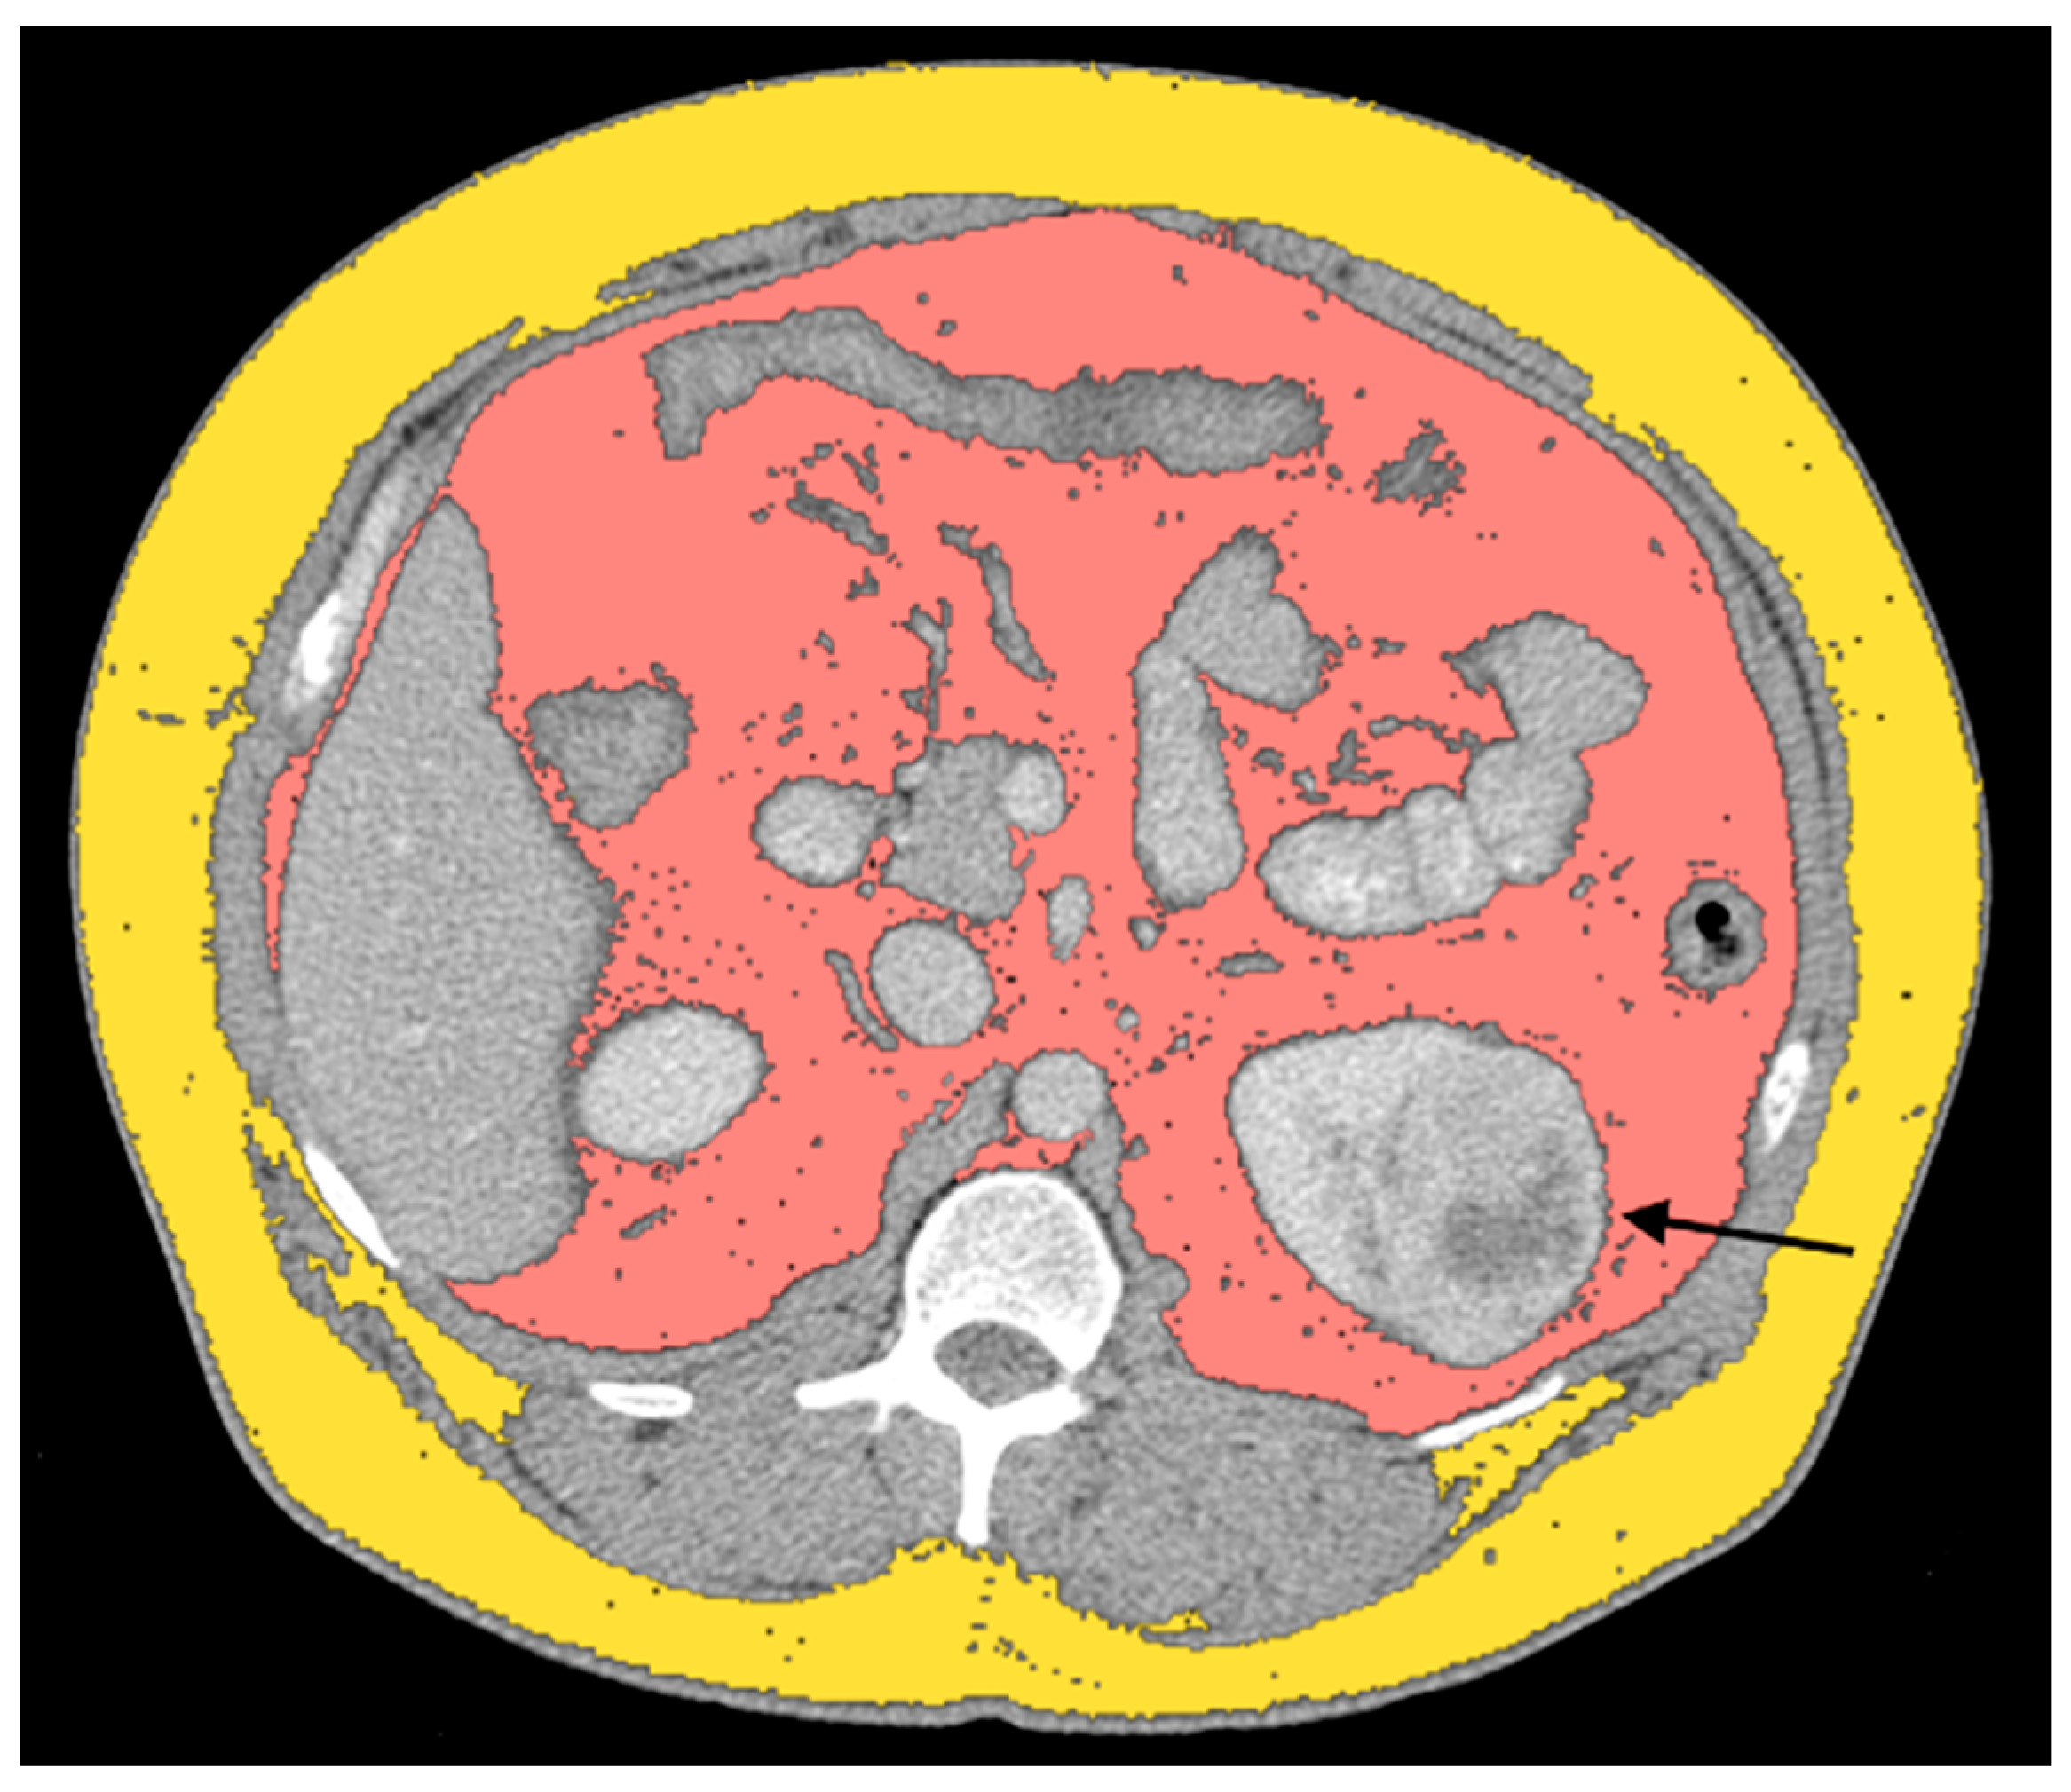

- Greco, F.; Mallio, C.A. Relationship between visceral adipose tissue and genetic mutations (VHL and KDM5C) in clear cell renal cell carcinoma. Radiol. Med. 2021, 126, 645–651. [Google Scholar] [CrossRef] [PubMed]

- Greco, F.; Tafuri, A.; Grasso, R.F.; Beomonte Zobel, B.; Mallio, C.A. Clinicopathological and Body Composition Analysis of VHL and TTN Gene Mutations in Clear Cell Renal Cell Carcinoma: An Exploratory Study. Appl. Sci. 2022, 12, 9502. [Google Scholar] [CrossRef]

| Greco et al., 2021 [24] | Relationship between VAT and genetic mutations (VHL and KDM5C) in clear cell renal cell carcinoma | 97 | CT | VHL, KD5MC | Increased amount of TAT, especially VAT, in the ccRCC-VHL and ccRCC-KDM5C groups. Statistically significant differences (i.e., increase in the ccRCC-VHL group) between control group and ccRCC-VHL group were obtained for TAT area (p < 0.001) and VAT area (p < 0.01). Statistically significant differences (i.e., increase in the ccRCC-KDM5C group) between control group and ccRCC-KDM5C group were obtained for TAT area (p < 0.0001), VAT area (p < 0.0001), and SAT area (p < 0.01). The ccRCC-KDM5C group showed a statistically significant increase in TAT area (p < 0.05), VAT area (p < 0.05), and VAT/SAT ratio (p < 0.05) with respect to the ccRCC-VHL group. | Without |

| Greco et al., 2022 [30] | Clinicopathological and Body Composition Analysis of VHL and TTN Gene Mutations in Clear Cell Renal Cell Carcinoma: An Exploratory Study | 54 | CT | VHL, TTN | Gene expression and overall survival was assessed on a large cohort of 483 patients and 533 tumor samples. There was a statistically significant difference in the VHL expression due to the decrease in VHL expression in pathological specimens compared to normal renal tissue. ccRCC patients with a VHL low/medium expression show a survival probability greater than 0.25 and a maximum survival greater than eight years. Moreover, the results showed a significant decrease in TAT, VAT, SAT, and TAM in the ccRCC-TTN group compared to the ccRCC-VHL group. A statistically significant difference of the VHL expression reduction in primary tumor (p < 0.0001) and a TTN expression increase in primary tumor (p < 0.0001) was shown. Statistically significant differences between the two groups were obtained for TAT (p < 0.01), VAT (p < 0.05), SAT (< p < 0.05), and TAM (p < 0.05) areas. | Without |